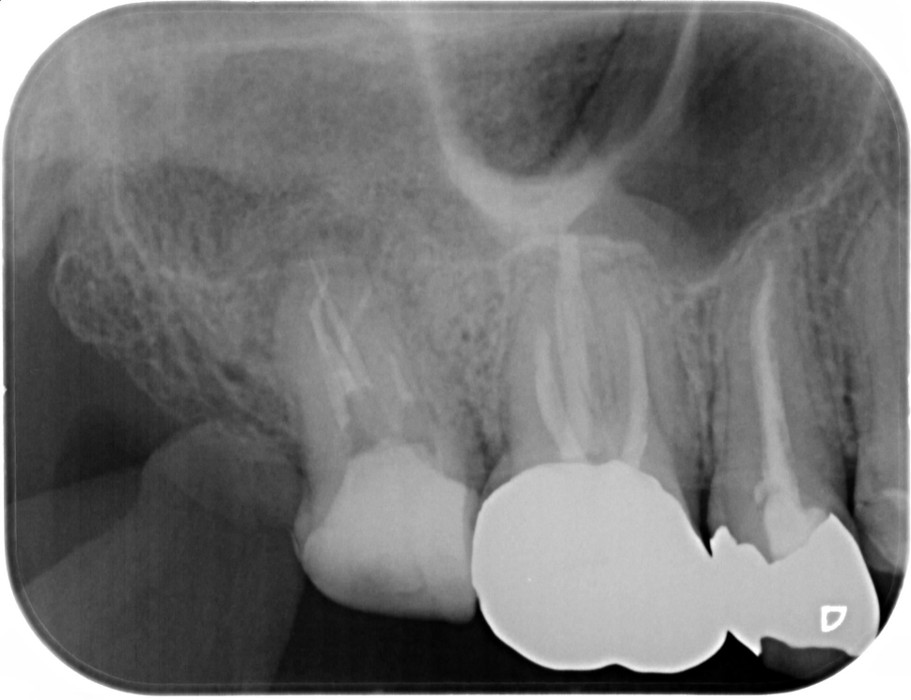

症例4

| 項目 | 詳細 |

|---|---|

| 患者様データ | 60代 女性 |

| 来院時の主訴 | 「残りの人生を健康的に噛めるようになりたい。」 |

| 医院の診断 |

虫歯の再発、歯周病を併発した慢性根尖性歯周炎 |

| 通院期間 | 1年間 |

| 来院回数 | 8回 |

| 治療費 | 480,000円(税抜) 《内訳》 精密感染根管治療100,000円、ファイバーポストコア20,000円、セラミック治療120,000円×3 |

| リスクと副作用 | ①根管治療歯は長期的には破折するリスク ②メインテナンスが必要 |

| ココがこだわりのポイント☝ |

ラバーダム防湿とマイクロスコープを使用して丁寧に治療を行いました。 再根管治療のため、殺菌性があり歯を補強することのできる根管充填材料を使用しています。 歯周病を併発していましたが、患者様の日々の歯磨きの努力により、改善することができました。 |